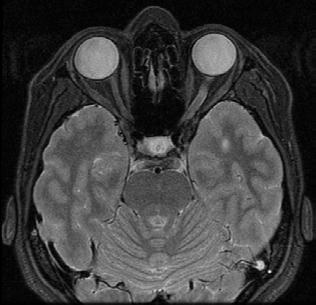

Figure 2. Multimodal imaging of right eye of a male diabetic patient affected by PDR and DME. 2A-B) UWF pseudocolor retinography (Optos Silverstone, Optos, UK) and corresponding magnification of macular region showing diffuse hard exudates and intraretinal hemorrages; 2C) OCT (Heidelberg Spectralis, Heidelberg Engineering Inc., Germany) displaying diffuse center-involving DME; 2D-E) Late phase UWF FA (Optos Silverstone, Optos, UK) and corresponding magnification of macular region presenting extense breakdown of BRB with perivascular leakage and non-perfusion areas, pooling effect compatible with MA and masking effect due to pre-retinal hemorrhages. Two leakage spots associated to possible NVs close to inferior vascular arcade; 2F) 3x3 B-scan OCT-A (Zeiss PLEX Elite 9000, Carl Zeiss, Germany) showing flow signal within pre-retinal NV.